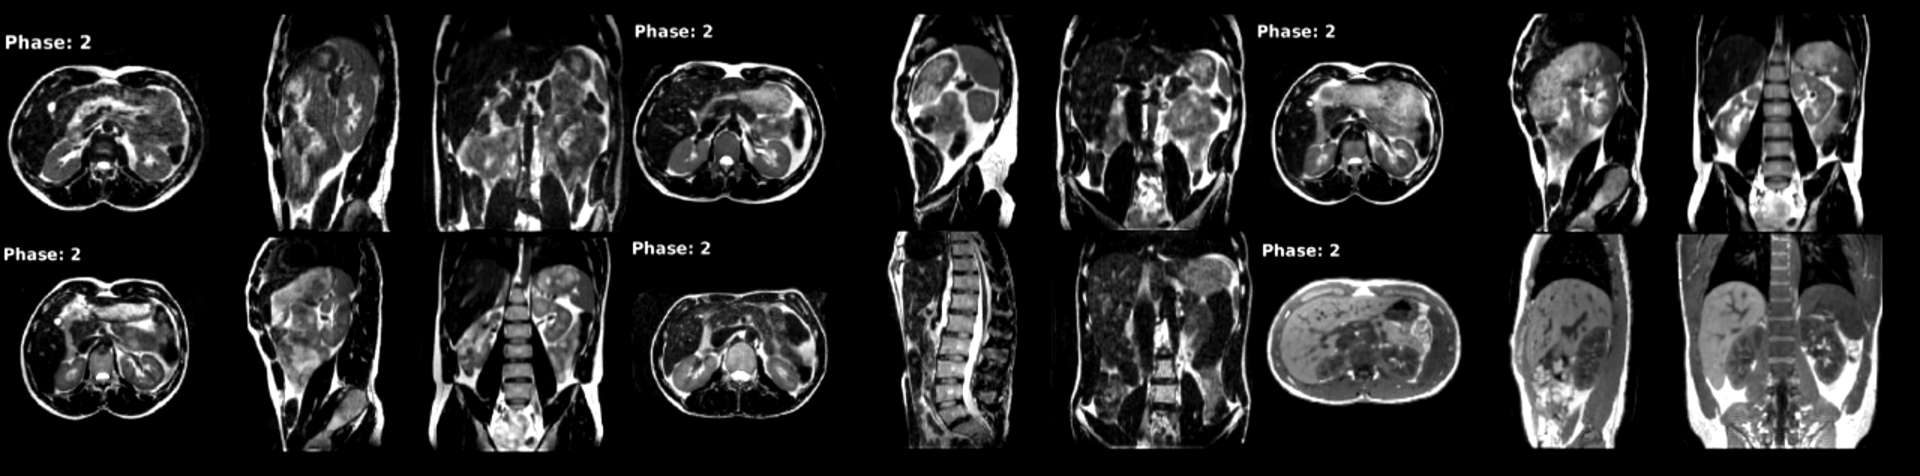

Refer to caption

Figure S1: Volunteer 3: TODO.

Figure S2: Motion compensated rCASPR images warped with the deformation vector fields used in the reconstruction. Top row shows volunteer 1-3 and bottom row volunteer 4-6. Note that the 4D-MRI was reconstructed using 10 respiratory phases, but 20 are shown here for visualization purposes. Video version can be found: https://surfdrive.surf.nl/files/index.php/s/xmcAwLXRp51izcG